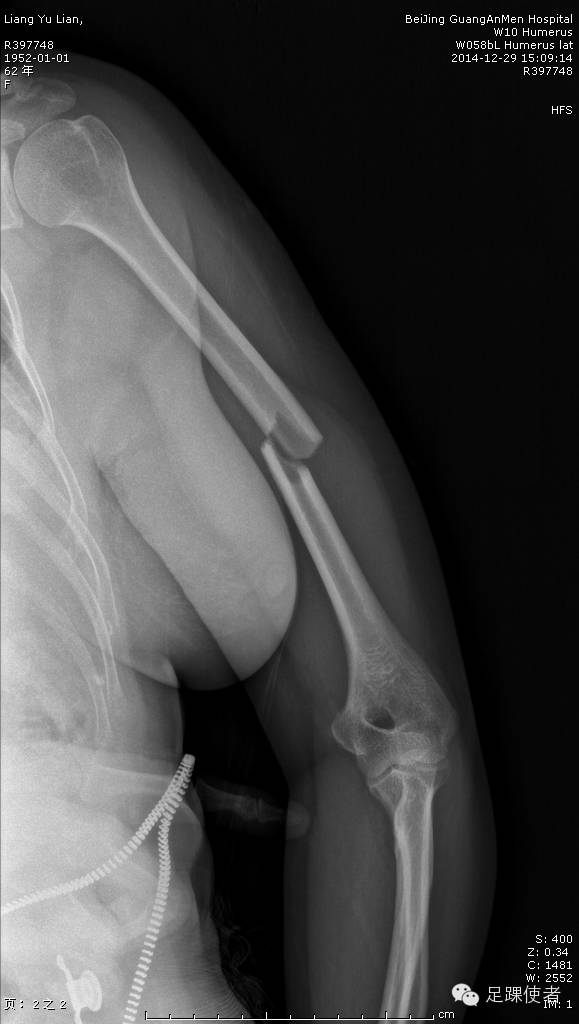

肱骨干骨折是上肢比较常见的骨折之一,过去肱骨干骨折的治疗需要经一个很大的切口进行手术,组织损伤广泛,出血多,还容易损伤重要的血管神经。

现在我们开展了微创治疗肱骨干骨折的新方法,只需经过两个小切口就可以复位骨折,并且放入一枚很长的钢板。即可靠地固定了骨折,又减小了组织损伤。